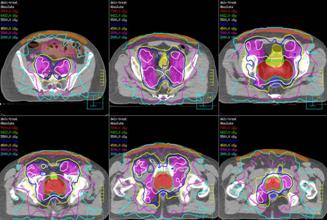

Photo: A radiation treatment plan for prostate IMRT.

Intensity modulated radiation therapy is an advanced form of 3D conformal that allows doctors to customize the radiation dose. It uses multiple small radiation beams to irradiate the tumor. The radiation of each beam is divided and can be set to deliver different intensities to focus on the tumor to spare the surrounding healthy tissue as much as possible.